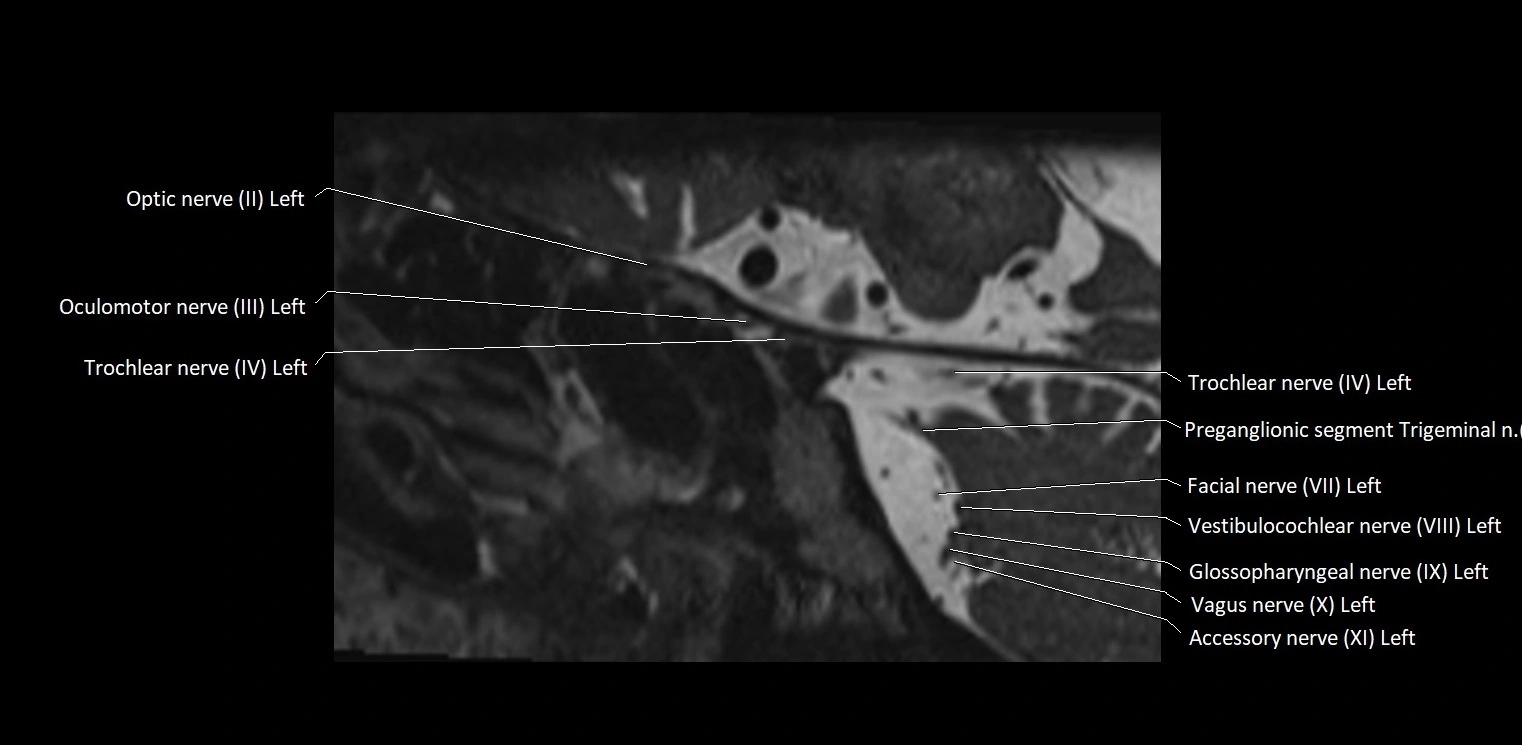

MRI Appearance

• The abducens nerve is a small, thin, linear structure

• Best visualized on high-resolution T2-weighted 3D MRI sequences (e.g., FIESTA or CISS)

• Seen as a hypointense (dark) line running from the brainstem at the pontomedullary junction, traversing the prepontine cistern, and entering Dorello’s canal under the petrosphenoidal ligament, then into the cavernous sinus, and finally the orbit

• May be challenging to visualize in standard MRI due to its small size

• Pathology may be inferred by absence, displacement, or enhancement of the nerve

MRI images

image